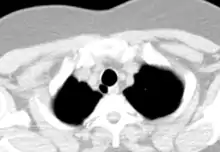

- CT scan of the thorax (axial lung window)